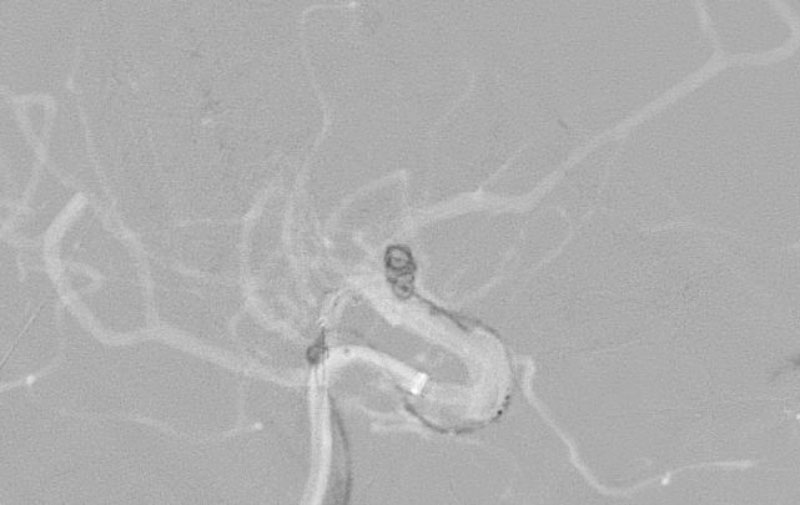

'25年11月

くも膜下出血

右内頚動脈後交通動脈

分岐部動脈瘤破裂

60代

救急外来

No.1593 手術前

No.1593 手術中

No.1593 手術後